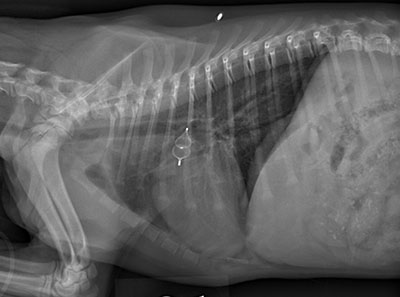

Blondie, a 2-month-old Shetland Sheepdog puppy, recently came to Auburn University’s Bailey Small Animal Teaching Hospital with a common but serious congenital heart defect — patent ductus arteriosus (PDA).

For Blondie and other dogs born with PDA, the condition results from a specific blood vessel – the ductus arteriosus – not closing after birth. The blood vessel connects the aorta and pulmonary artery in fetal dogs, allowing blood to bypass the non-functioning lungs. When it remains open, oxygenated blood flows back into the lungs instead of circulating throughout the body.

From there, the team moved special catheters through her heart and into her PDA to place an occlusion device. The occlusion device, a tiny implant, permanently plugs the abnormal vessel and prevents heart failure. The Bailey Small Animal Teaching Hospital maintains an inventory of several different types of occlusion devices that can be deployed to fit the size and type of PDA in its patients.